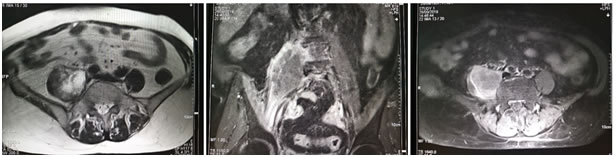

Investigations include complete blood count, differential count, C reactive protein, ESR, urine routine and culture, blood culture, renal and liver function tests, vaginal and endocervical swabs. Ultrasound is the first line investigation for radiological diagnosis, however the diagnosis is often missed because of lack of clinical suspicion. Even with clinical suspicion, it is diagnostic in only 60% of cases 6. Sonography is also essential to rule out the evidence of any retained products of conception. Simple abdomen radiography can demonstrate blurring of the psoas muscle region, and air enhancing duodenal or renal contour, although its diagnostic value for psoas abscess is restricted . The sacroiliac joint, the lumbar spine, and intervertebral disks should be carefully examined. If a lesion is too small to reveal soft tissue gas, spinal destruction, mass effects or unusual iliopsoas, plain films would only reveal negative findings 7. CT is the most accurate investigation for diagnosis of iliopsoas abscess with reported sensitivity of 100% and specificity of 77% 8. Few studies state that the magnetic resonance imaging (MRI) can differentiate soft tissues more accurately, producing a clear view of the abscess wall and its surrounding structures without the use of a radiocontrast agent, thus, making the MRI a better choice than the CT scan 9. On CT scans, an abscess may manifest as enlargement of the iliopsoas muscle by a low-attenuation lesion [FIG 1, FIG 2]. The lesion typically displays rim enhancement after the intravenous administration of contrast material . Abscesses appear as areas of low signal intensity at nonenhanced T1-weighted MR imaging and as areas of high signal intensity at nonenhanced T2-weighted MR imaging [FIG 3]10. Secondary findings include obliteration of the surrounding fascial planes, bone destruction, and gas bubbles. CT is more sensitive than MR imaging for demonstrating gas bubbles.11

Figure 3

Figure 1: Coronal and Axial CT images showing normal appearance of bilateral psoas muscles which show uniform attenuation and well defined margins; Figure 2: Non contrast axial and coronal CT images showing right psoas abscess; Figure 3: T2w axial and post contrast T1FS axial and coronal images showing right psoas abscess